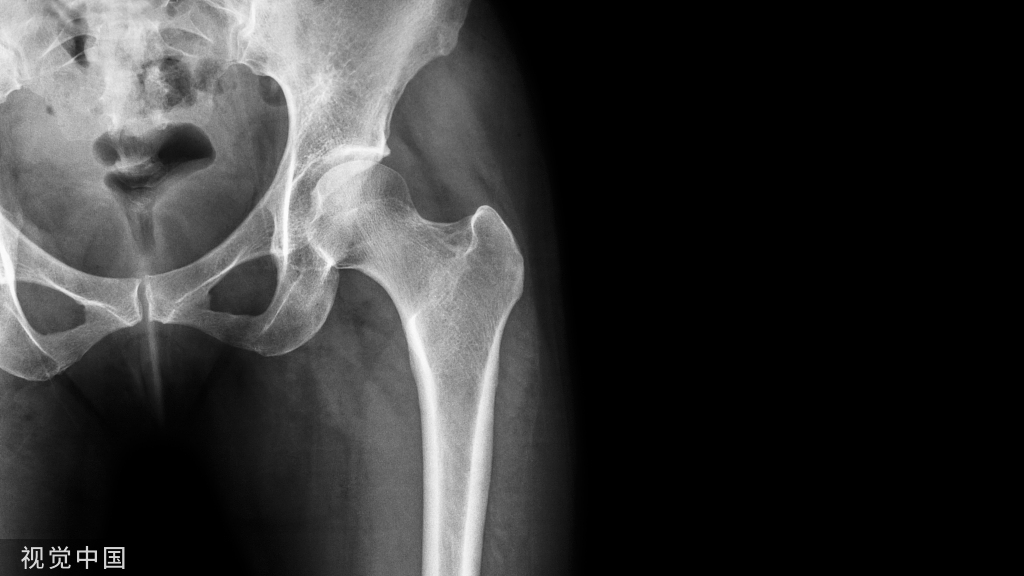

骨水泥己广泛应用于骨科临床,骨水泥固定可保证术后假体的即时稳定,在骨组织-骨水泥-假体界面上无任何微动,允许术后早期负重,疗效肯定。